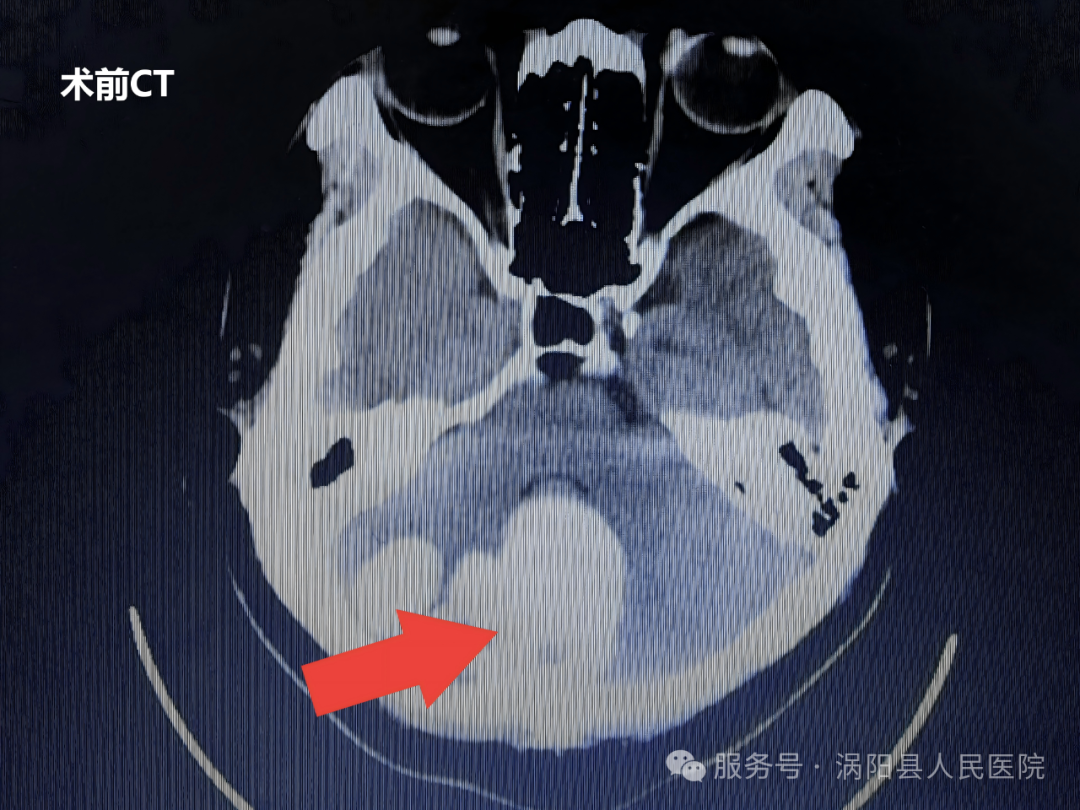

3月9日,一位特殊的小脑巨大占位性病变患者入住我院。经检查,患者颅内病变体积较大,临床考虑先天性疾病可能性大,病变已对小脑形成明显压迫,且合并脑积水症状,生命危在旦夕。更为特殊的是,患者为聋哑人,且家庭经济困难,属低保对象。

3月13日,手术正式开展。在全身麻醉下,由神经外科主任医师周维广、王超领衔的手术团队,在手术显微镜下精准施治。该手术采用后正中入路,手术视野深、操作空间狭小,对主刀医生的心理素质和专业技术都是极大考验。手术团队凭借丰富的临床经验、娴熟的显微外科技术,历经6小时细致操作,成功完整切除病变组织,并将标本送检病理检查。术后复查CT显示,手术效果理想,患者颅内情况良好。